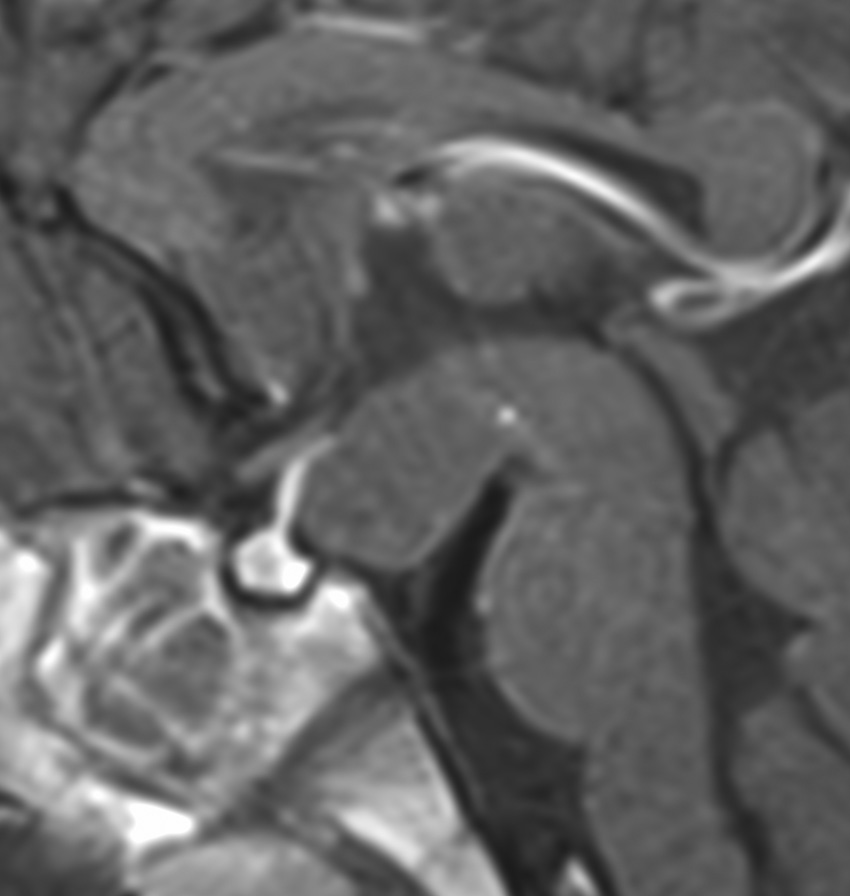

術後のMRIです,pterional approach でしか摘出できない腫瘍でした

高い位置がとどかず少し取り残しました

gelastic seizureは減荷されましたが残り,術後に視野欠損を後遺しました